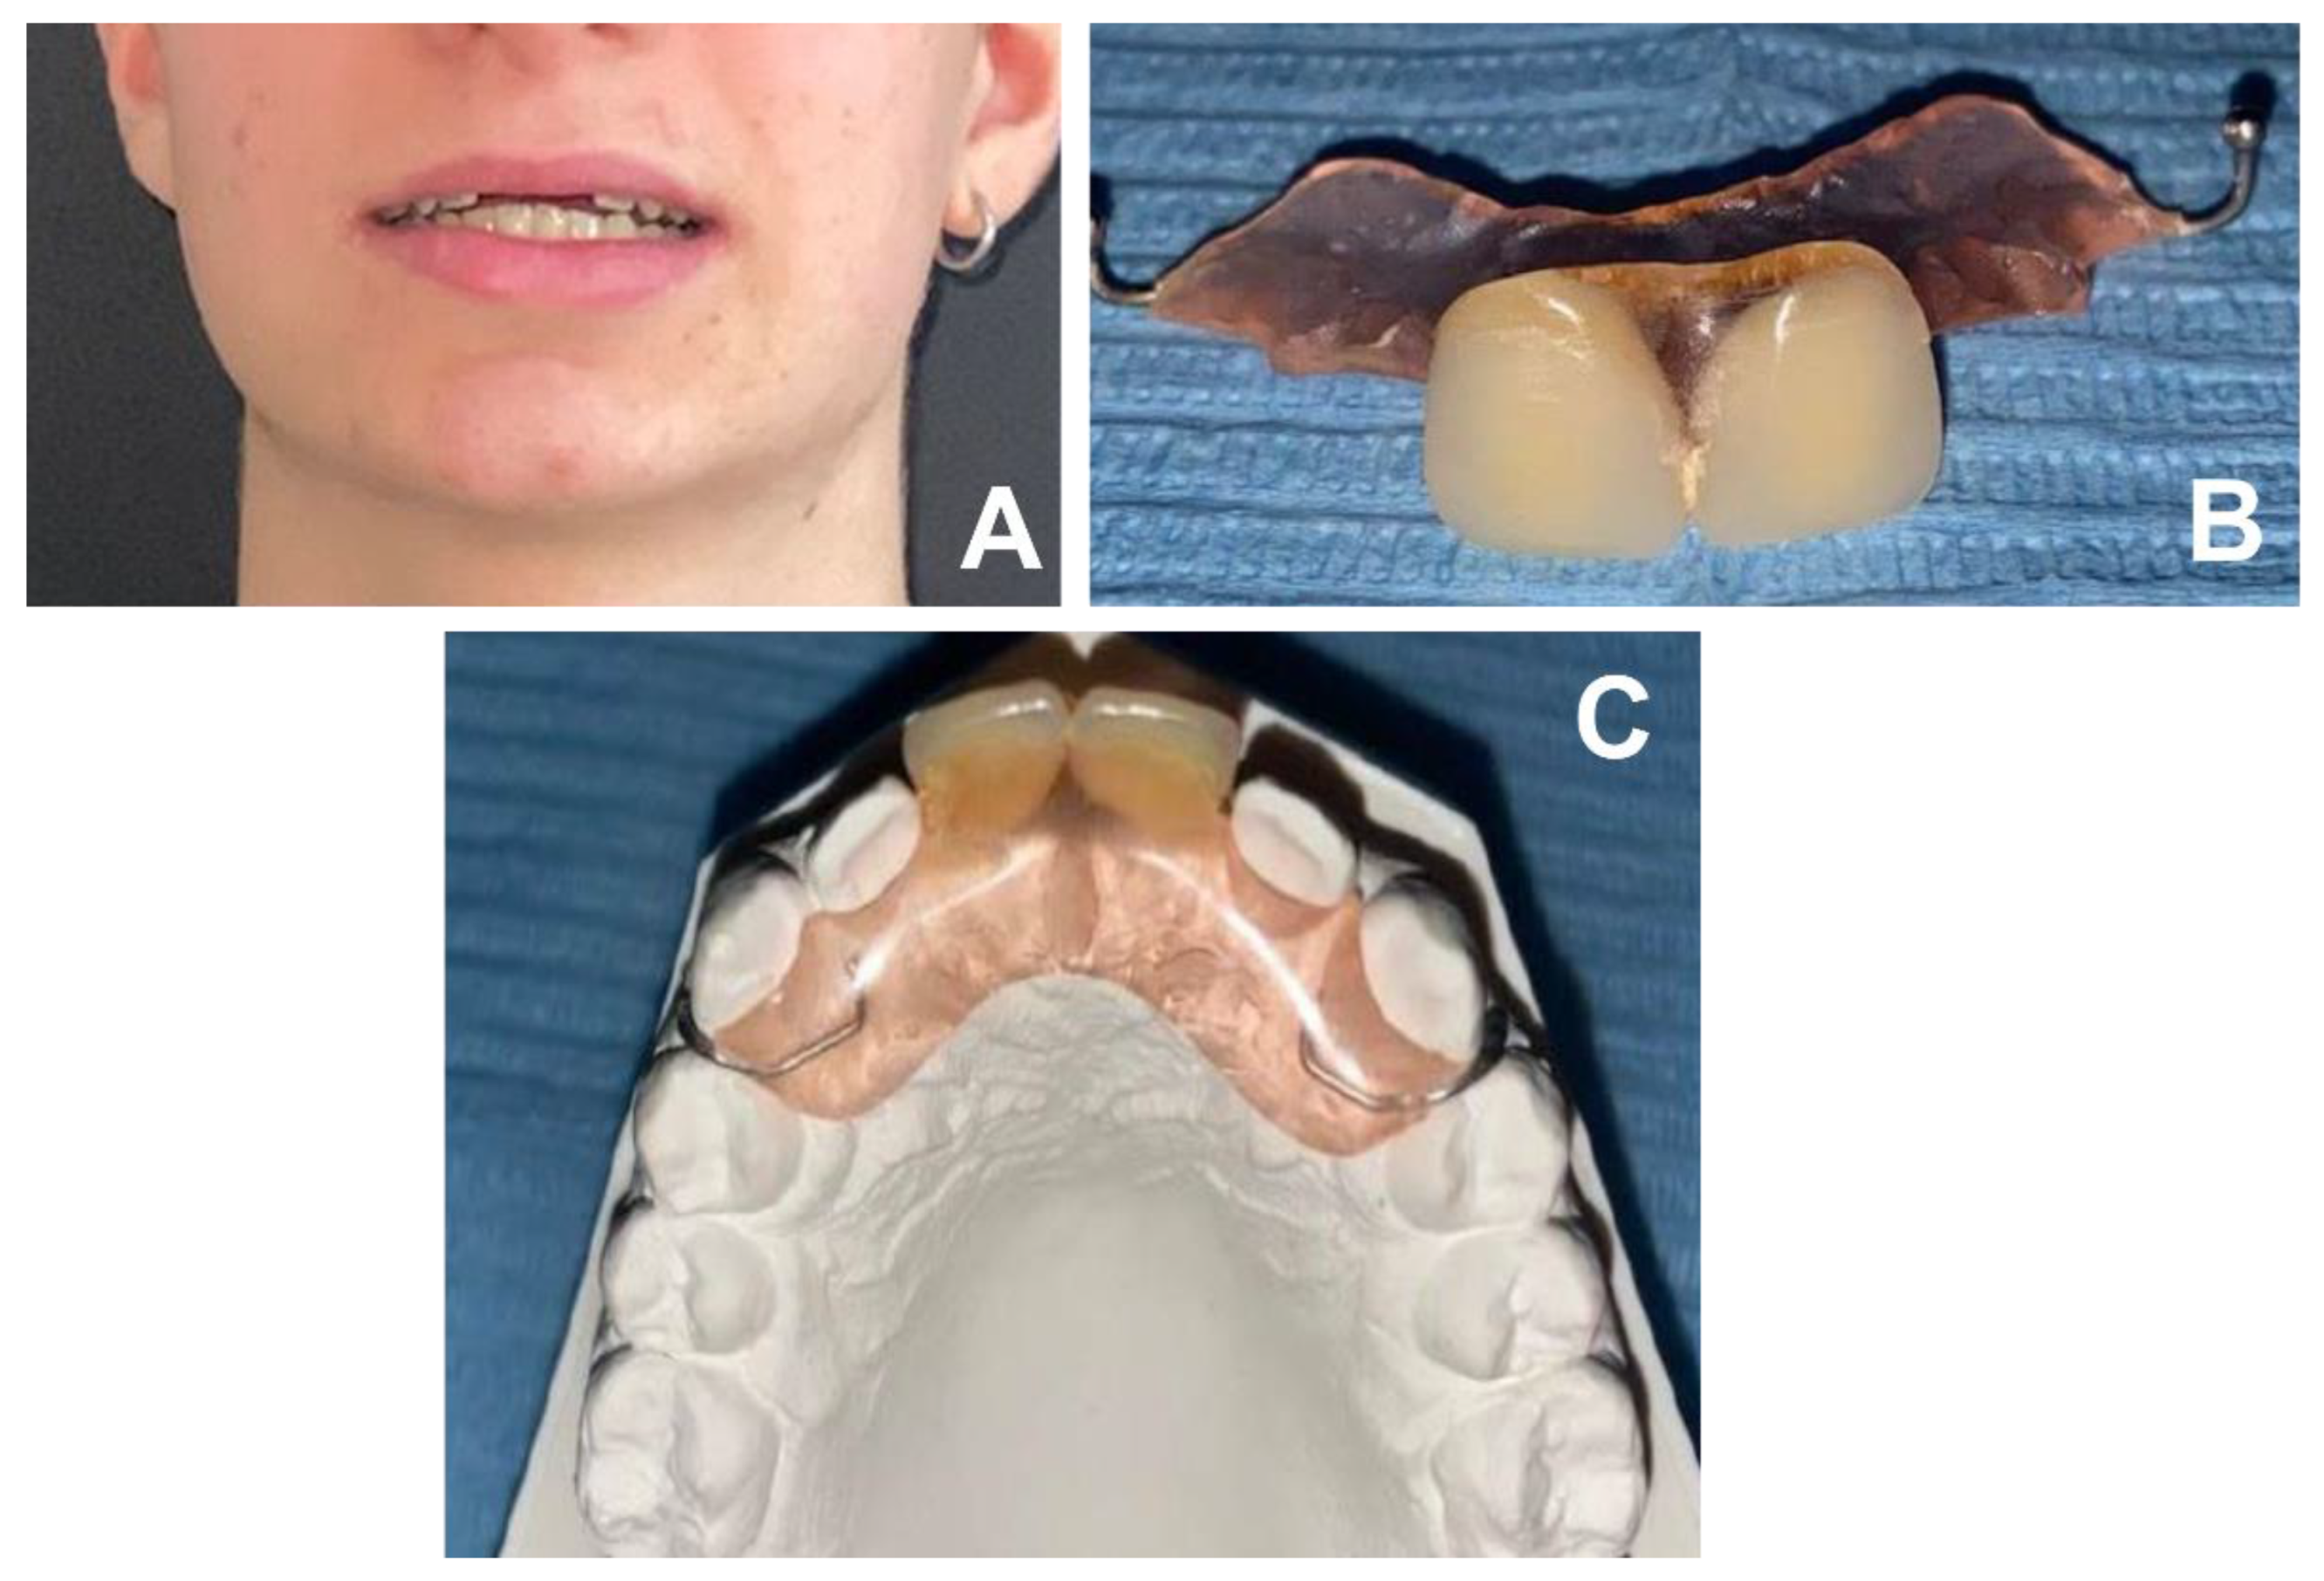

2. Case Report

2.1. Clinical History

2.2. Clinical Exams and Diagnosis